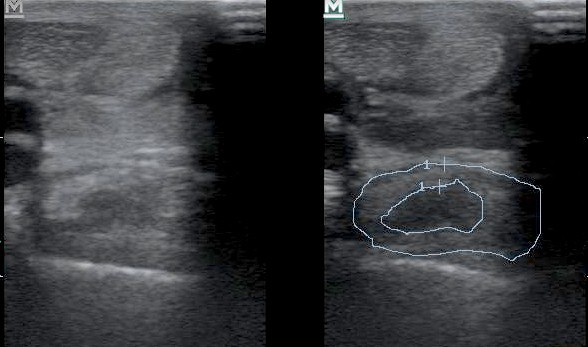

Súlyos fokú egyenítőszalag sérülés keresztmetszeti képe. Bal oldalon a sima, jobb oldalon a bejelölt felvétel.

Mindkét végtagon érzéstelenítés és ultrahang vizsgálat alapján lehet a diagnózist kimondani az esetek többségénél. Az ultrahang lelet enyhébb sérülések esetén kétes lehet, ezt MR vizsgálattal lehet megerősíteni. A kezelés alapja a kontrollált mozgatás.